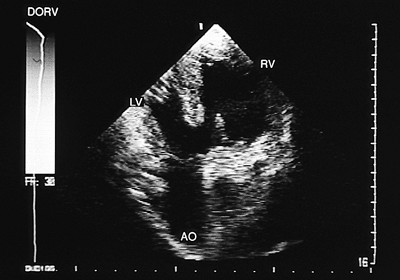

Right Ventricular Double Outlet

In the right ventricular double outlet both great arteries arise mainly or completely from the right ventricle. Any type of A–V connection can coexist. The position of the vessels is variable. When they are side-to-side or the aorta is anterior, the emergence of the vessels is parallel. When the aorta is posterior and right, the great arteries cross in space. Often the underlying anomaly is tetralogy of Fallot with aortic overriding of >50%.

FIGURE 8.2.52. Double outlet right ventricle. Transgastric view shows aortic (AO) septal override. LV, left ventricle; RV, right ventricle.

The principal findings observed with transesophageal echocardiography are discussed in the following paragraphs.

Overriding of >50% of the posterior vessel over the interventricular septum is evident in recordings of both transverse and longitudinal planes (Fig. 8.2.52). The connection of both vessels with the right ventricle can be observed in longitudinal images (Figs. 8.2.53 and 8.2.54). When only monoplanar recordings can be obtained, multiple sections at various levels should be visualized to demonstrate that the great arteries are located on the same side of the interventricular septum (Fig. 8.2.55).